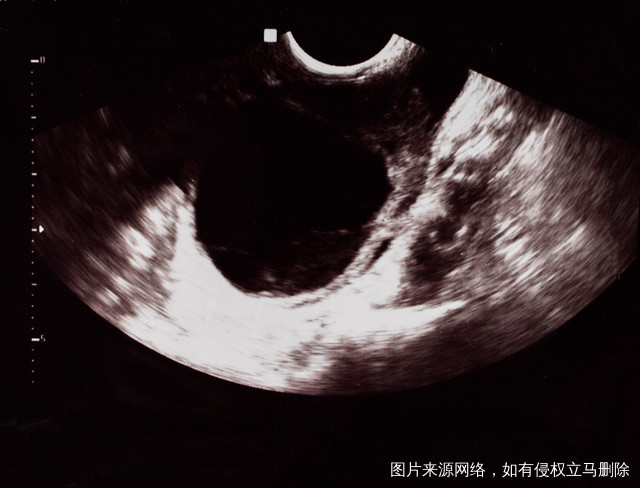

什么办法可以提高试管成功率?提高试管婴儿的成功率,在做试管前,是可以先都夫妻双方的身体进行调节的,调节好了在做试管,可以大大提高试管的成功率。女性可以在做试管前先提高卵子的质量,调整好子宫内膜的状态;而男性在做试管前,把精子的质量调整好;好的子宫状态,高质量的卵子和精子是试管婴儿成功的关键所在。